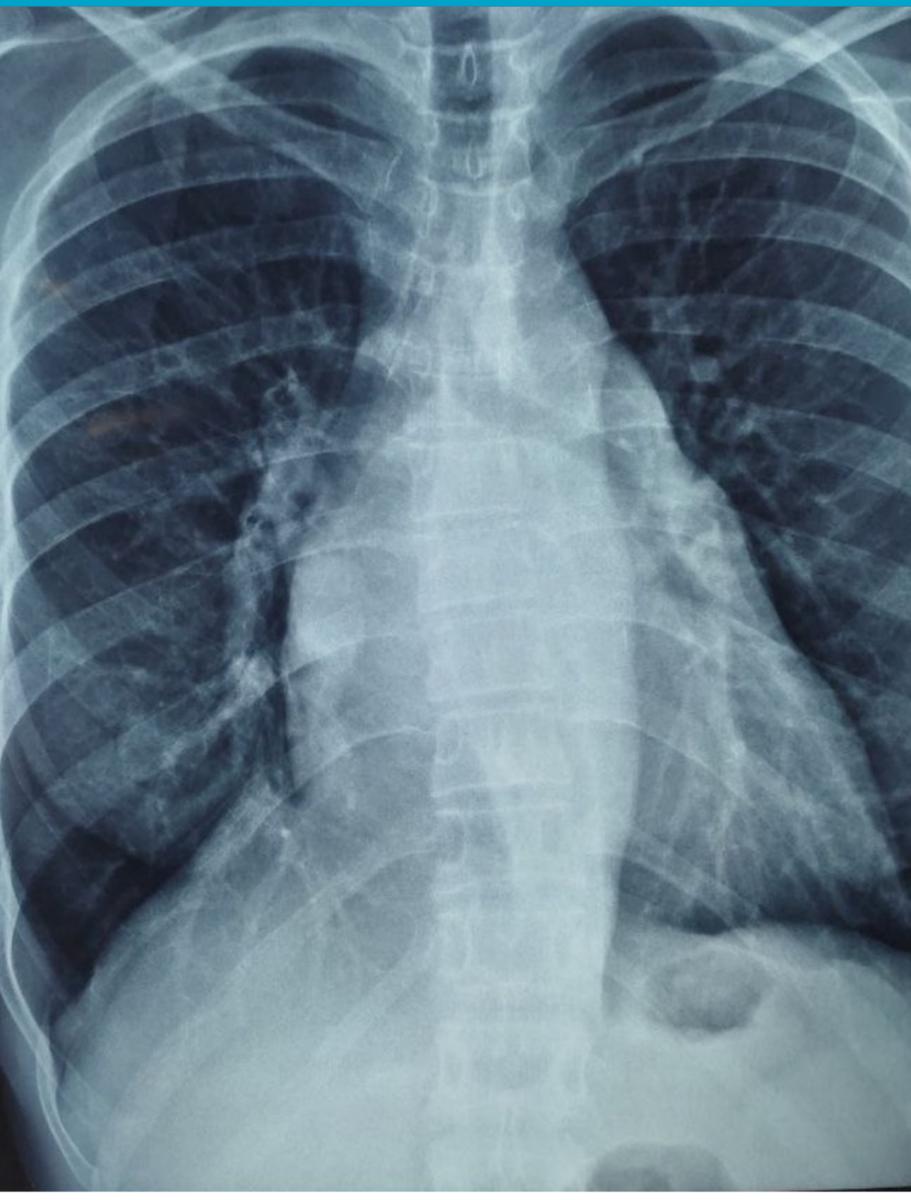

She had a history of hypertension and cachexia. The chest X-ray raised suspicion of aortic calcification, confirmed by a noncontrast CT scan, which demonstrated severe circumferential aortic calcification (porcelain aorta) with calcification-free femoral arteries (figures 1, 2).

Figure 1: CXR showing the porcelain aorta.